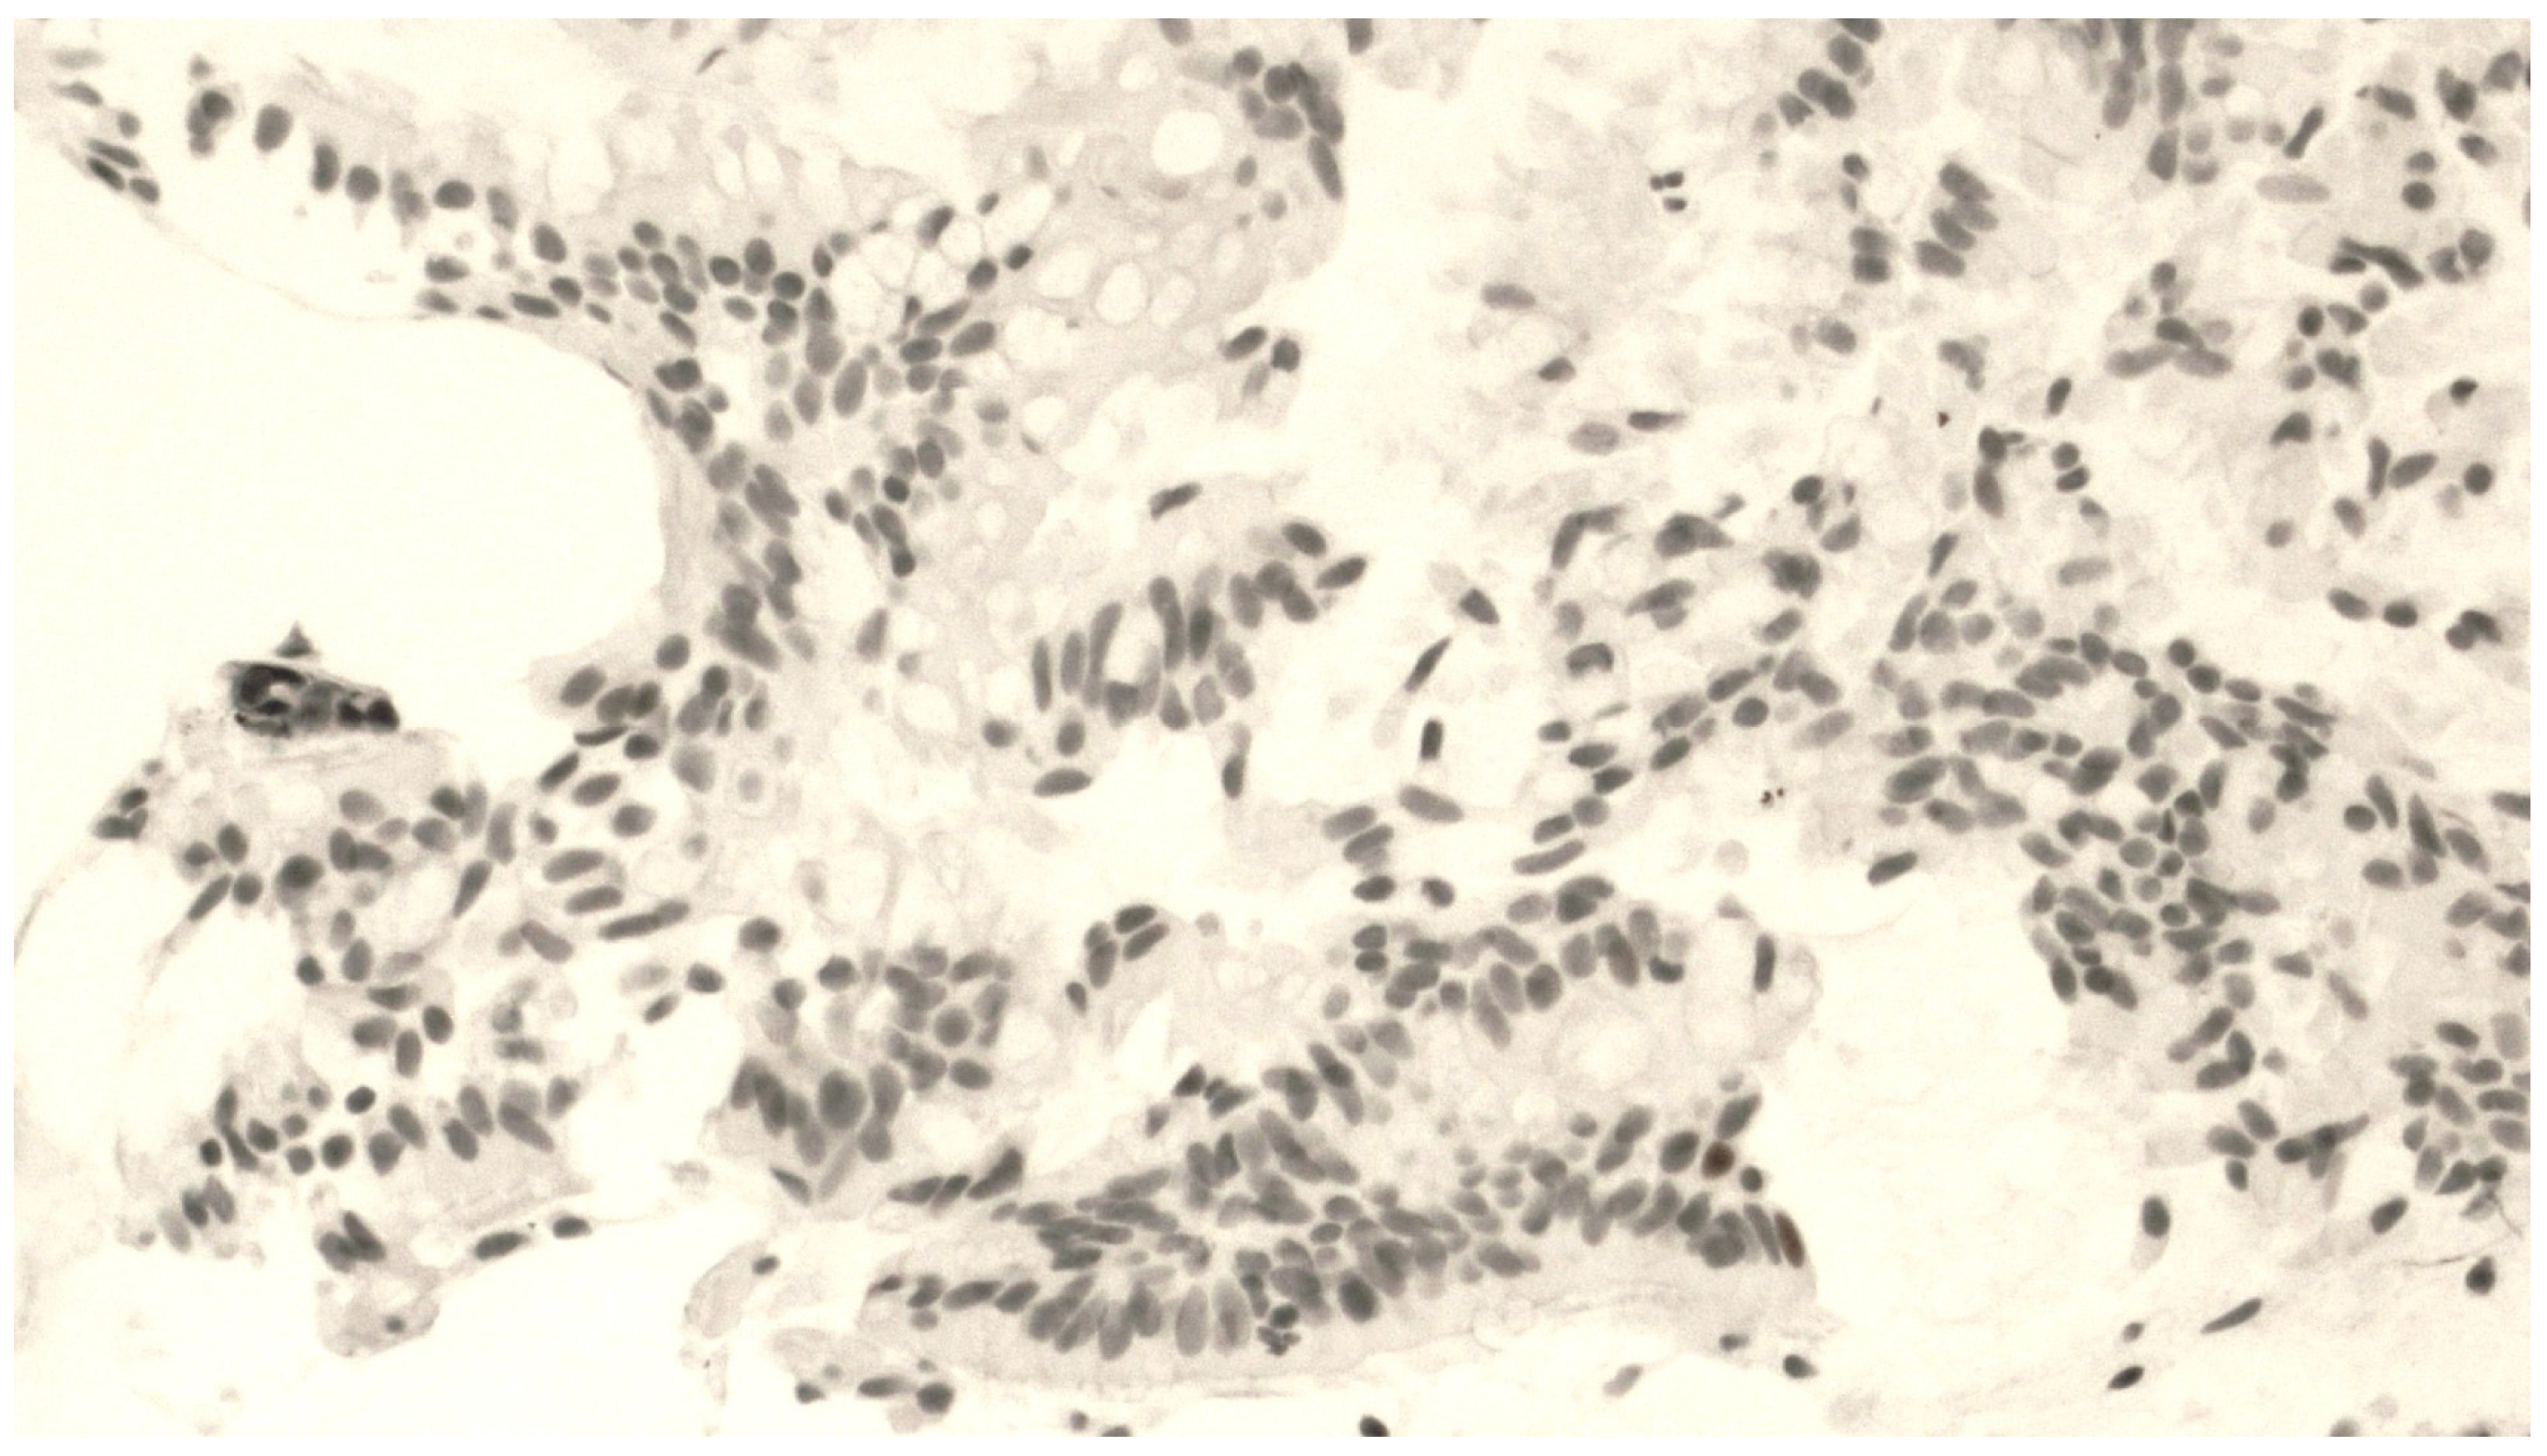

The mean number of p63+ BPCs was 36.6 ± 7.3 cells. Figure 1 shows a representative staining of bronchial biopsies for p63 expression.

Figure 1.

Fragment of bronchial mucosa stained by an anti-p63 antibody. A number of positive cells (corresponding to progenitor basal cells) are distributed along the base of the epithelium at 400× magnification.

We found an inverse correlation between FEV1% of predicted values and the number of p63+ BCs (r = −0.614, p = 0.019) (Figure S1). The correlation between p63+ bronchial cells and FEV1 expressed in liters was also statistically significant (r = −0.55 and p = 0.041) (Figure S2).

No differences in p63+ cell counts were found among patients with different histologic tumor types (i.e., large cell carcinomas, squamous cell carcinomas, adenocarcinomas, or small cell carcinomas). However, the localization of the p63+ cells was significantly higher in biopsies from the trachea and main bronchi compared to more distal areas (p = 0.040) (Table 2).